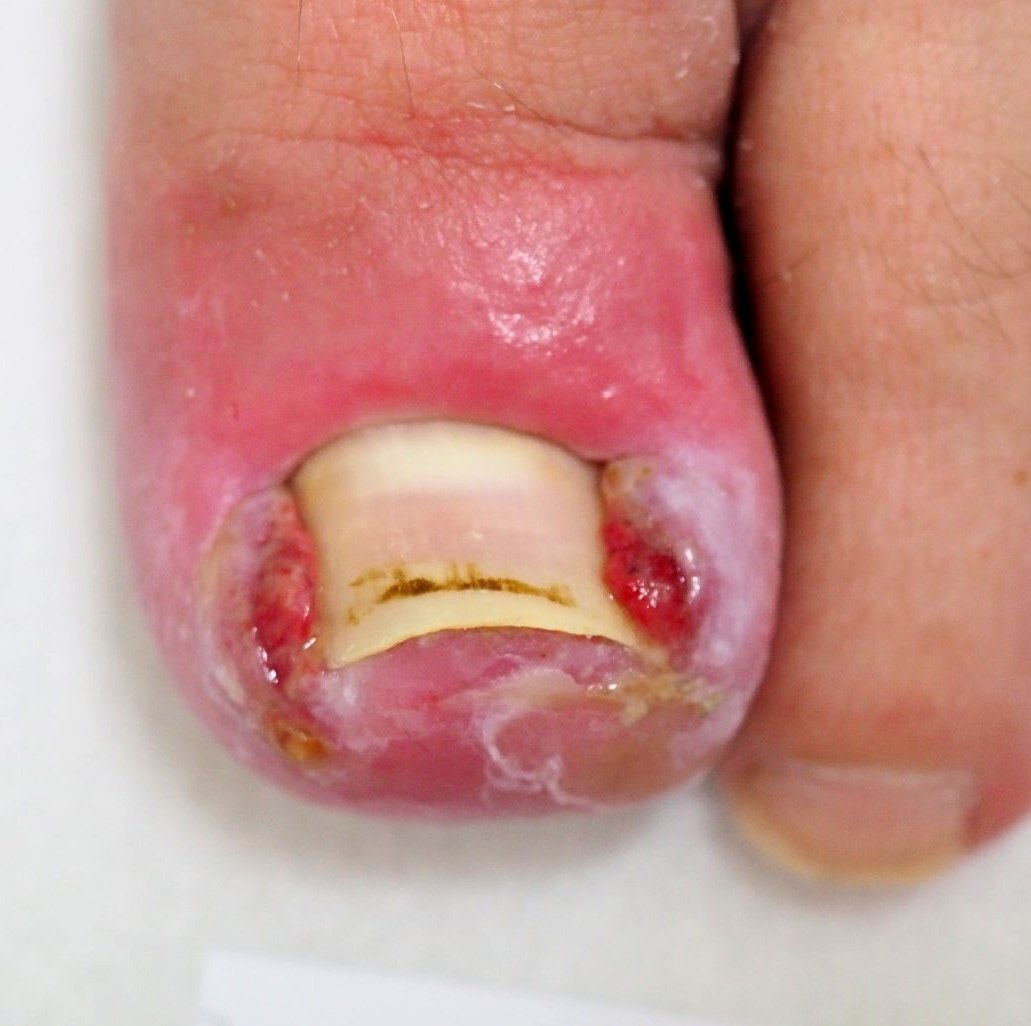

2.) Akutfall Hühnerauge

Hühnerauge subungual (unter der Nagelplatte)

Bild 3

die wieder funktionell und ästhetisch verschlossene Nagelplatte (nach abgeschlossenem Heilungsverlauf)